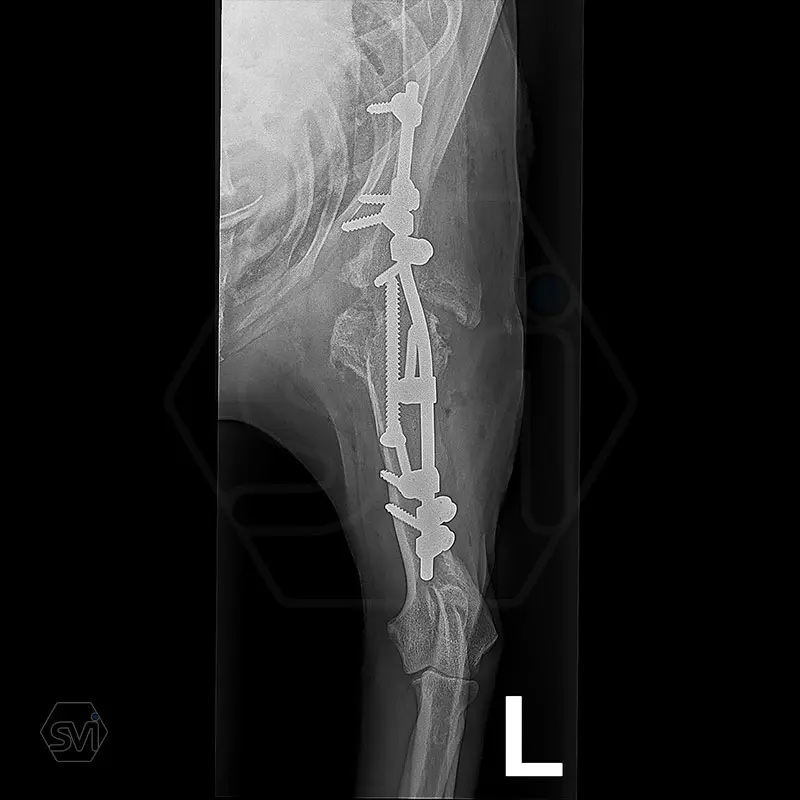

Arthrodesis is typically an area where the advantages of SOP-LC are clearly visible.

There is no weak point in bridging the joint, which is inevitable in a plate bridging. Another great advantage is that the clamps can be placed according to anatomical needs, on either side of the rod and the screws can be inserted in any direction. Maximum stability is provided by the locking clamps, which is especially advantageous in a thin bone (scapula) or a bone with a porotic or thinned cortex (leg that has been used less for a long time). We have used the system several times in reoperations due to a broken plate.

In our case, we created a shoulder arthrodesis on an 11-year-old 16kg female beagle dog with a 2.7 SOP-LC system and 4-4 clamps. The dog developed chronic arthritis and arthrosis, the biopsy did not confirm a tumor, only chronic inflammation.